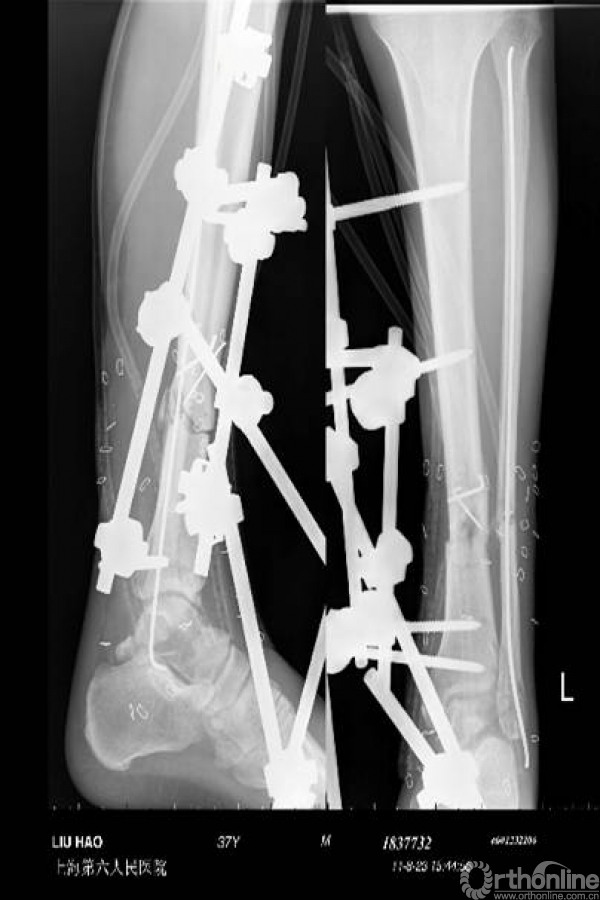

图1 男性患者,34岁,因交通伤致左胫腓骨开放性骨折(Gustilo IIIB型),术前广泛软组织损伤,胫前动脉及腓动脉断裂,骨折严重粉碎(a,b);

急诊予清创、外固定支架及腓骨弹性钉固定骨折,修复胫前肌腱和伸趾肌,采用VSD技术治疗创面(c,d);